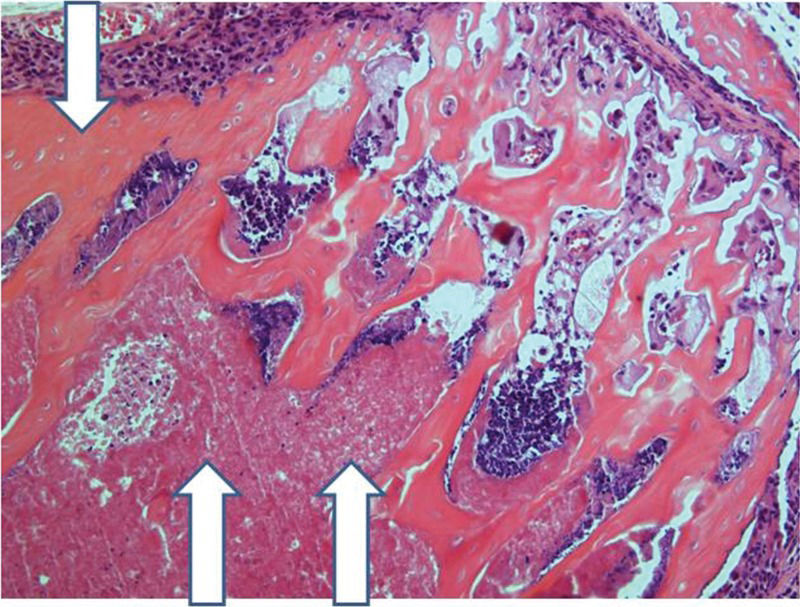

After 30 days, edema was no longer conspicuous. Some areas exhibited bone resorption. The bone marrow did not change substantially compared with that at 15 days (Figure 11). By 60 days, areas exhibiting extensive destruction of the bone and bone marrow could be identified. Nevertheless, as at other time points, the femur showed a generally heterogeneous pattern. Depending on the anatomical location, areas that were in fairly good histological shape were identified, whereas other areas revealed severe damage (Figure 12).

Implanted femur histology, 60 days (H&E, 100 X): Bone (upper arrow) and bone marrow (lower double arrows) degradation is more advanced. However, in keeping with the findings at 15 and 30 days, the pattern is not homogeneous, with seriously damaged areas, along with a better preserved femur.